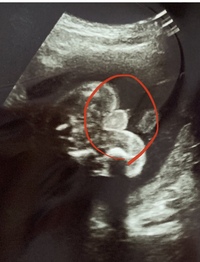

睾丸 エコー 画像-精巣(睾丸)の痛みや違和感、しこり、腫れなどの症状の診断や治療の役に立ちます。精巣や 精巣上体 ※1 の形や大きさ、内部の評価、精巣周囲の血管を調べます。この検査により、精巣癌、精巣捻転、精巣上体炎、陰嚢水腫、精液瘤などがないかが分かります。 エコー写真、おまたのあたりの白い点は睾丸でしょうか? 17週の写真です。 とくに性別判定のためにもらった写真ではありません。たまたま先生が渡してくれた写真です。 性別をきく予定はありませんでしたが、この写真のおまたの部分で男の子かな?と気になってしまいました。 上に

28週です これは睾丸で間違いないでしょうか お尻の後ろの方にあるのか Yahoo 知恵袋